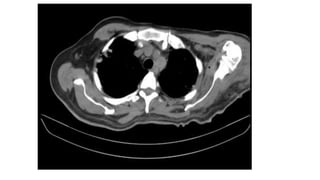

CT CHEST:

Ct chest

• Multiple varying size cavitatory lesions along with areas of

consolidation involving both lungs

• Left subscapular and Deltoid abcess , sclerosis of humerus

head

S/o

• Multiple septic emboli i/v/o abscess in the left shoulder

D/D:

• Cavitatory metastasis

• Vasculitis are less likely

Fibrotic strands and interstitial thickening seen involving both

the lungs - represent sequelae of prior infection